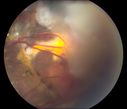

Vasoproliferative Tumor 7 Years after Retinal Detachment Repair519 views65 year old female presents 7 years following retinal detachment repair with peripheral white mass with hemorrhage.Mar 07, 2020